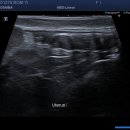

• 선부중앙동물의료센터 | 과잉진료없는 안산동물병원 추천 | 내돈내산 • 솔직후기•중성화수술 | 안산선부중앙동물의료센터

의료센터는 언산 선부동 한양산호상가 2층에 위치 해 있어요. 선부중앙동물의료센터 경기도 안산시 단원구 선부광장1로 69 단지내상가동 2층 205-1호 선부중앙동물의료센터 영업시간 월-일 10:00~19:00 접수마감 18:30 점심시간 13:00~14:00 선부중앙동물의료센터(@sunbu_amc) • Instagram 사진 및 동영상 팔로워 167명...

Be brave!(2026-01-24 17:58:00)